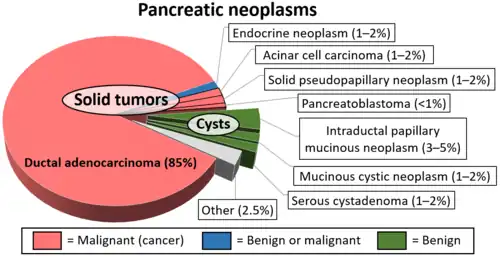

Acinar cell carcinoma of the pancreas, also acinar cell carcinoma, is a rare malignant exocrine tumour of the pancreas. It represents 5% of all exocrine tumours of the pancreas, making it the second most common type of pancreatic cancer.[1] It is abbreviated ACC. It typically has a guarded prognosis.

Diagram by Mikael Häggström, M.D. - ^ a b c Pishvaian MJ, Brody JR (2017). "Therapeutic Implications of Molecular Subtyping for Pancreatic Cancer". Oncology (Williston Park). 31 (3): 159–66, 168. PMID 28299752.